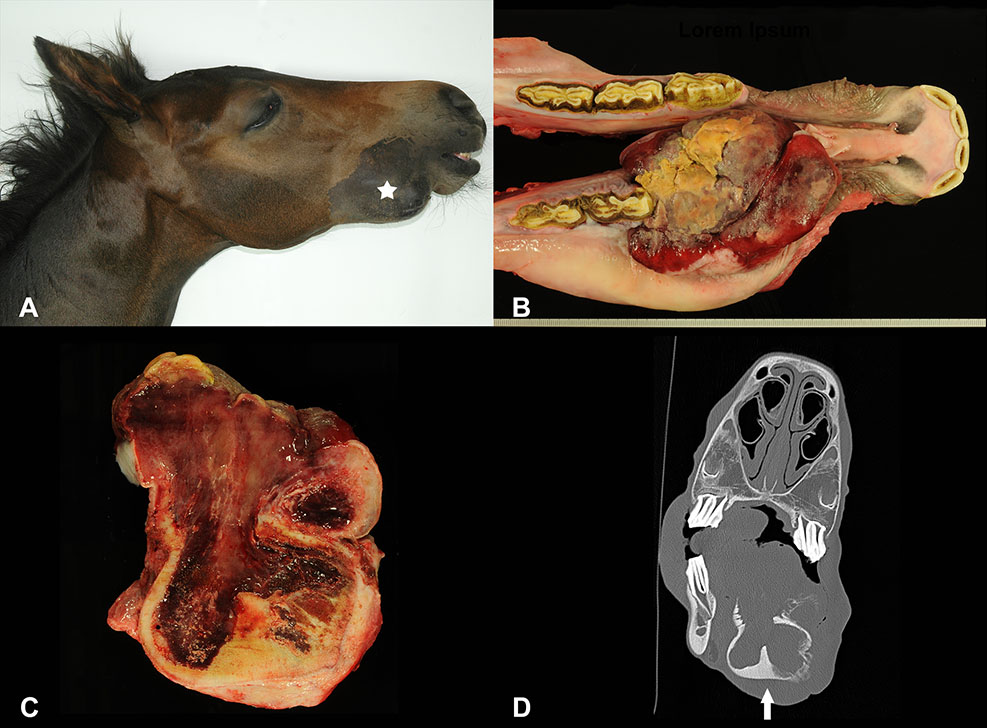

At necropsy the animal was in a good nutritional condition. An ~10 x 7 x 7 cm large, firm, elastic swelling of the right mandible (Figure 1A, white star) localized at the diastema was found. The mass was covered by gingiva and caused a protrusion of the mandibular bone with consecutive loss of Pd2 (Figure 1B). The multinodular oral growth exhibited extensive ulceration. Moreover, it compressed and displaced the surrounding osseous tissue. The cut surface of the proliferation was homogenously red and of gelatinous consistency (Figure 1C). Corresponding changes were also detected in CT images (Figure 1D). On the right side of the tongue, affecting the middle to caudal third, there was a focal, brownish, moderately hyperkeratotic area of ~10 x 2 cm. At the left cranial aspects of the tongue, there were multifocal ulcerations, most likely resulting from trauma due to tooth bites. The right mandibular lymph node measured 8 x 2.5 x 2.5 cm. Moreover, there was a 6 x 1 x 0.4 cm sized ulceration at the margo plicatus of the stomach.

Figure 1

Swelling on the right mandible (A; white star) of a foal, showing extensive growth and consecutive loss of the first deciduous premolar (B). The cut surface was reddish and of gelatinous consistency (C). Transverse CT image of the oral mass involving the right mandible (D; arrow).